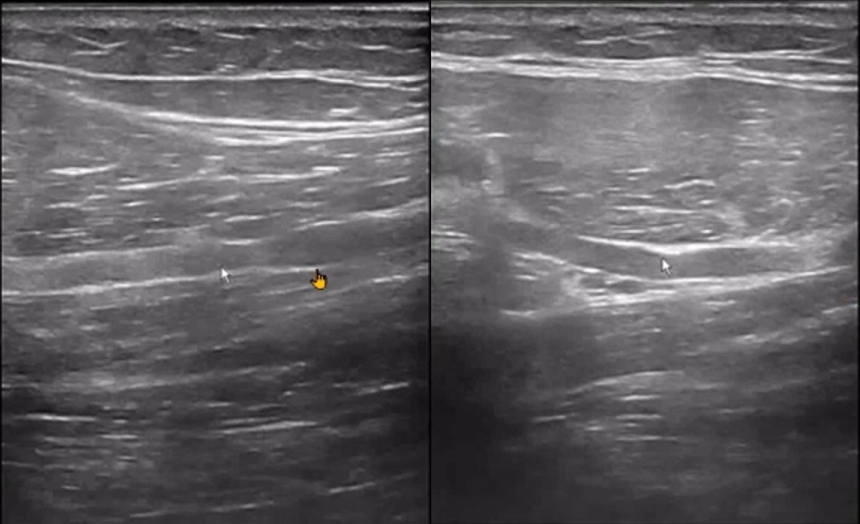

The handheld ultrasound machine indicated ulnar nerve compression in the right upper limb, likely due to synovial proliferation within the cubital tunnel and an external nerve sheath cyst in the forearm.

For healthcare professionals considering the purchase of a handheld ultrasound machine, cases like this underscore the importance of high-resolution imaging in diagnosing nerve compressions and related conditions.